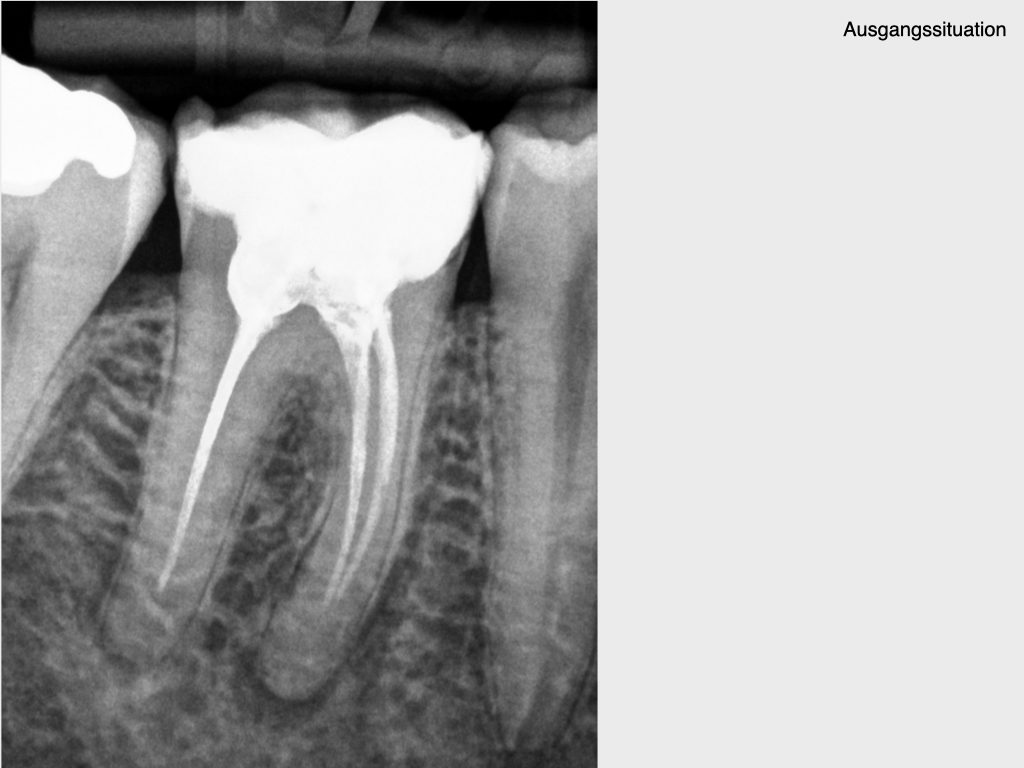

und wieder ein Fall aus der Reihe Pick, pick